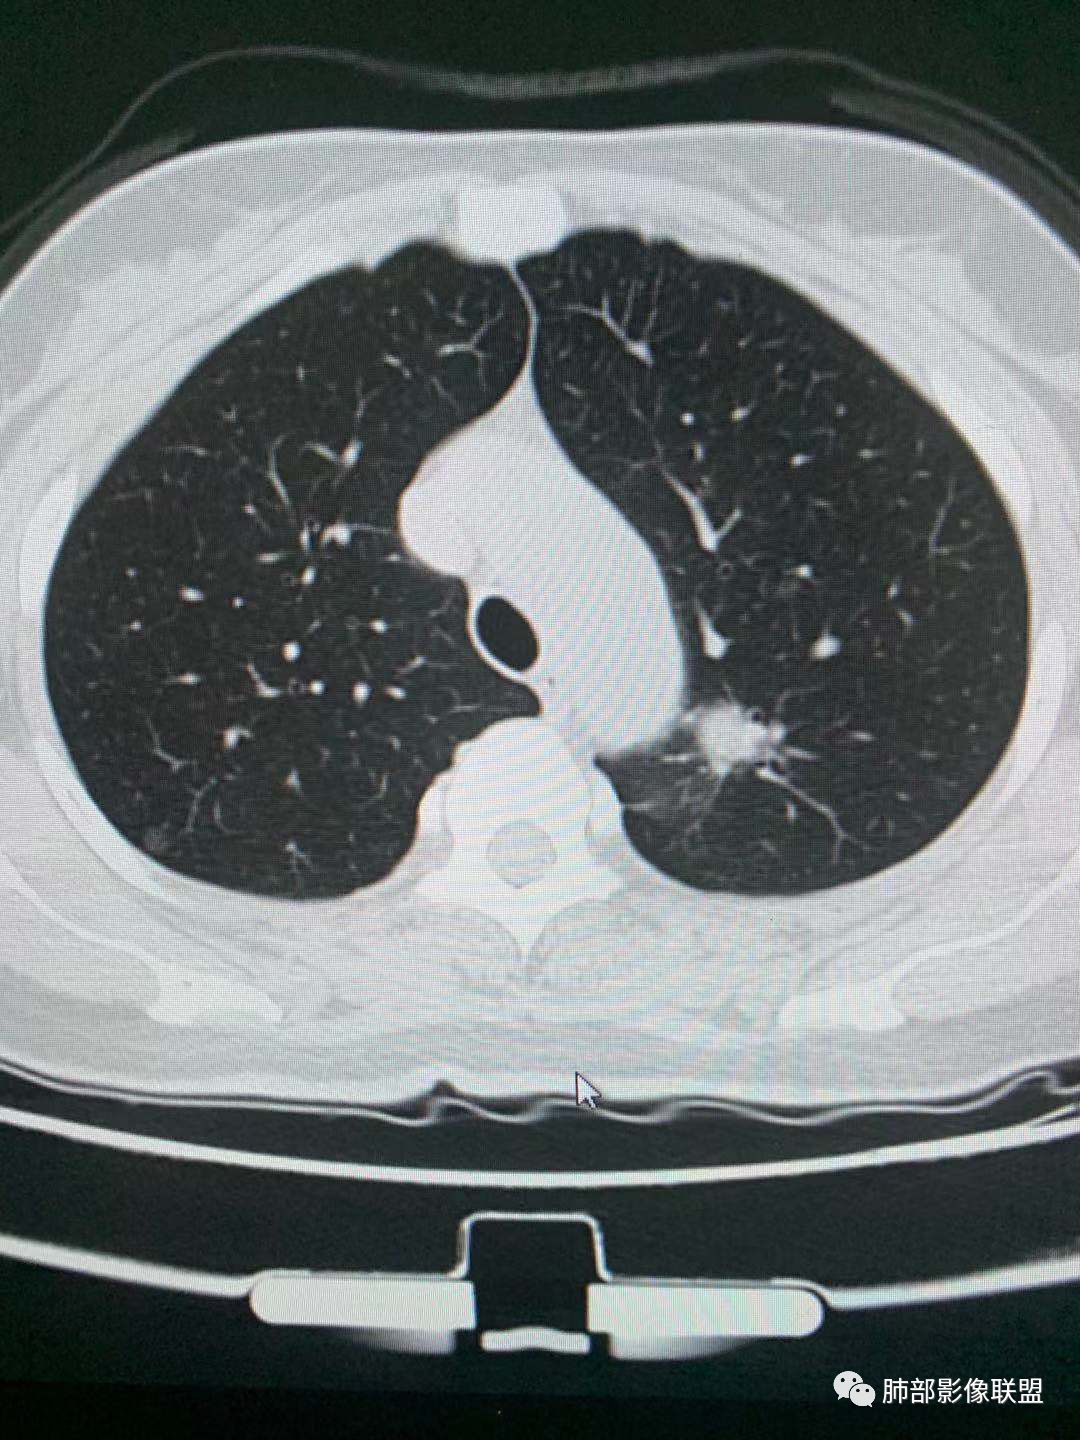

二.左肺上叶前段磨玻璃结节:

该结节较大,边界清楚,小叶间隔阻挡特征相当明显,微浸润腺癌的诊断几乎没有争议!

三.右肺上叶胸膜下结节及左肺上叶血管旁结节,尽管都是磨玻璃密度,但都比较小且边缘特征不明显,恶性征象未显露,处置并无特殊,定期复查!